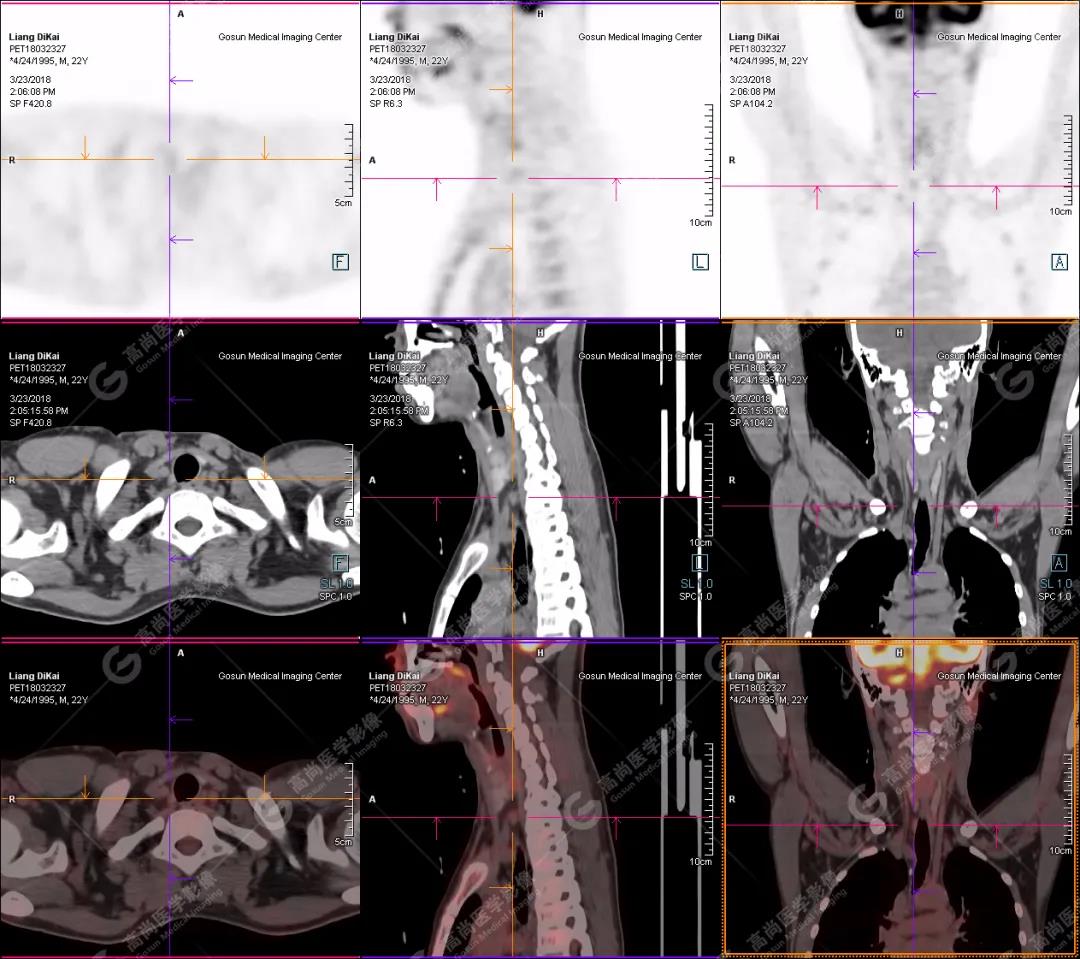

1.右肘關(guān)節(jié)周圍、骶尾部皮下、雙側(cè)臀部、盆腔左側(cè)壁及左側(cè)大腿根部肌肉、肌間隙多發(fā)結(jié)節(jié)狀、片塊狀及不規(guī)則巨塊狀高密度鈣化灶,伴代謝不均勻輕度增高,考慮為鈣質(zhì)沉著癥;

2.甲狀腺雙葉后方多發(fā)(右2個,左1個)小結(jié)節(jié)狀軟組織影,部分代謝輕度增高,多考慮為甲狀旁腺腺瘤。